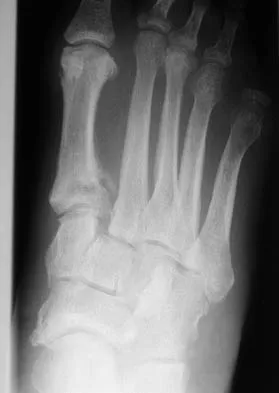

Question 67 High Yield

Corrective osteotomy of fibular malunions, with appropriate lengthening, even in the presence of early arthritis, has been shown to decrease ankle pain and increase stability. Reduction and bone grafting of the medial malleolar nonunion is also needed. There is no evidence supporting the use of intra-articular steroids or hyaluronic acid in the ankle joint. Lateral talar displacement of even 1 mm has been reproducibly shown to decrease tibiotalar contact by 40% to 42%, causing a predisposition to arthritis. Weber D, Friederich NF, Muller W: Lengthening osteotomy of the fibula for post-traumatic malunion: Indication, technique and results. Int Orthop 1998;22:149-152. Lloyd J, Elsayed S, Hariharan K, et al: Revisiting the concept of talar shift in ankle fractures. Foot Ankle Int 2006;27:793-796. Offierski CM, Graham JD, Hall JH, et al: Later revision of fibular malunion in ankle fractures. Clin Orthop Relat Res 1982;171:145-149.